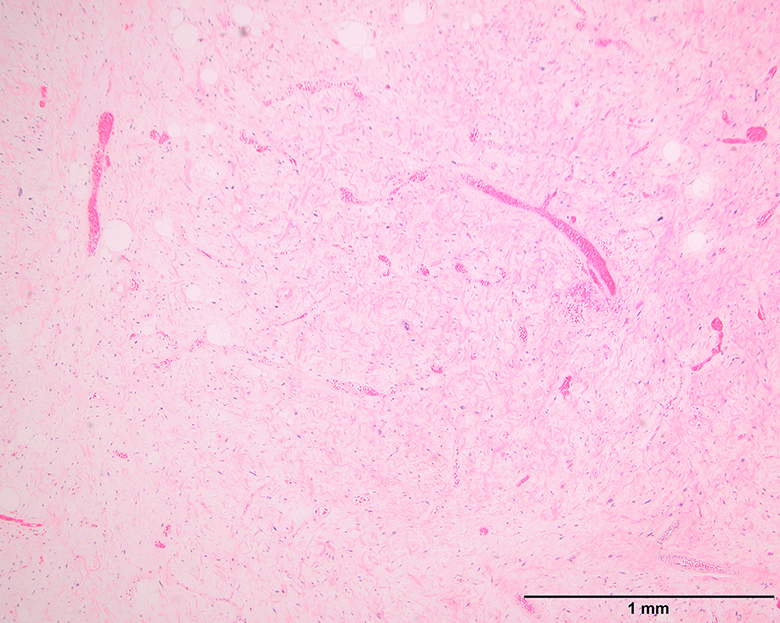

Microscopic (histologic) images

Contributed by Michael Clay, M.D., Melanie Bourgeau, M.D. and AFIP

Morphologic variability: